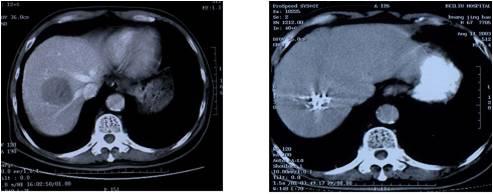

原发性肝癌治疗前                            放射粒子植入后肿瘤显著 缩小、灭活